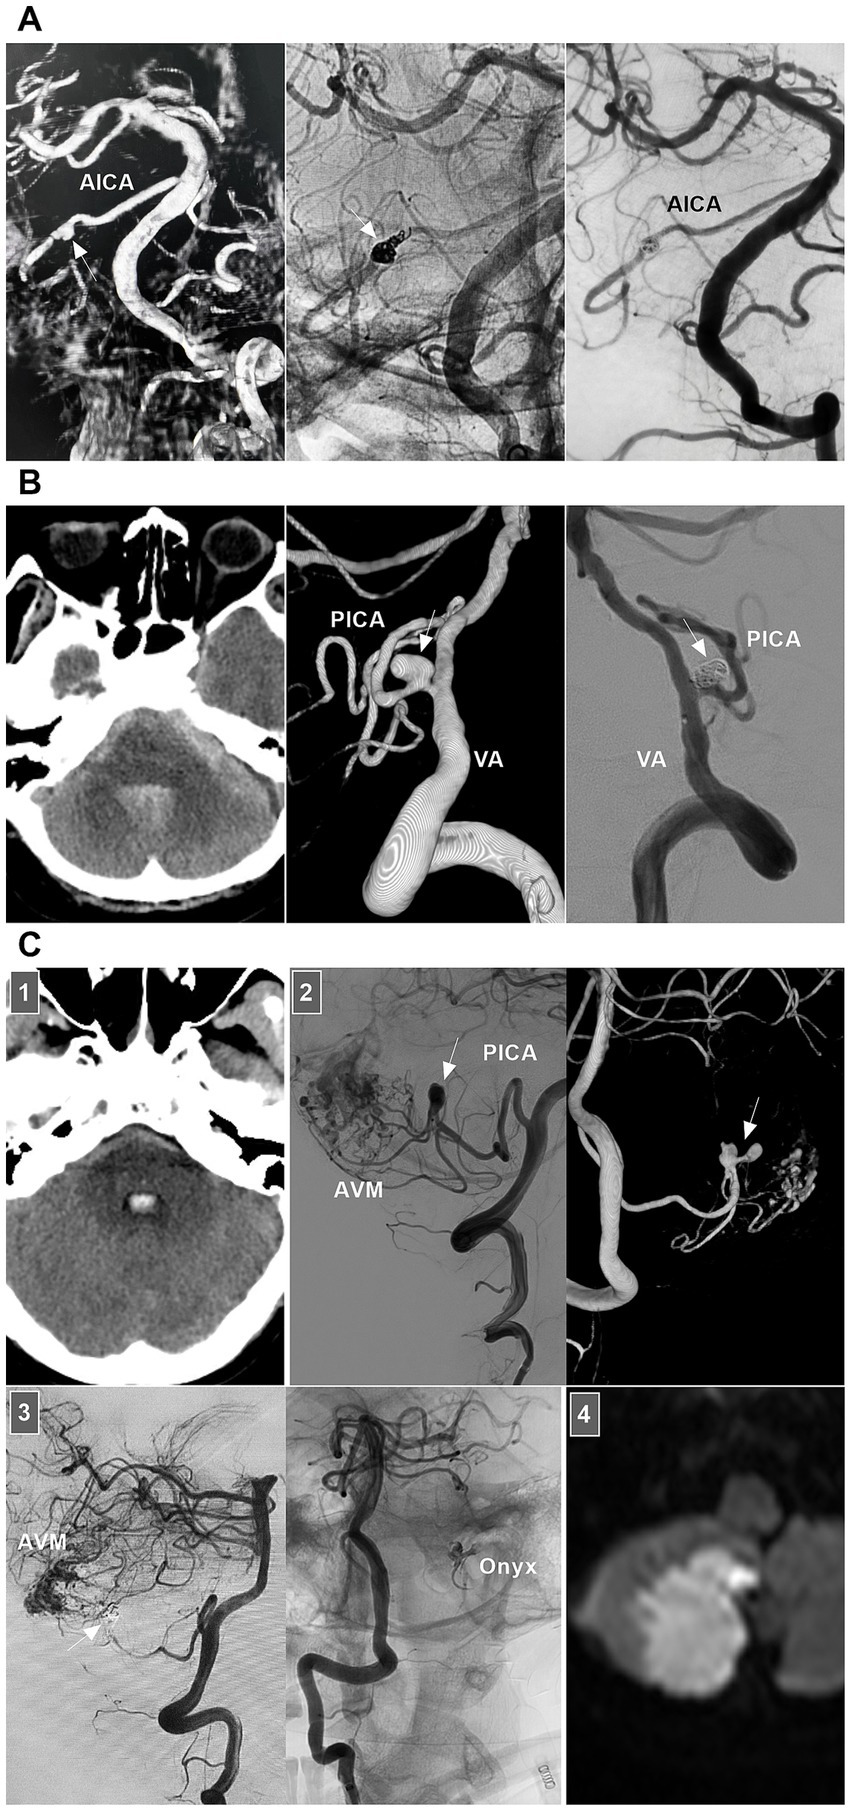

8.2.1 BA dissections

Little is known about the clinical manifestations of spontaneous BA dissections; these lesions may be asymptomatic and silent or may present with SAH, brainstem compression, or ischemia (71). For BA dissections with brain ischemia, conservative anticoagulation treatment is the standard approach. Chronic occluded BA dissection can have no or minor symptoms (Figure 10A) (72). However, acute occluded BA dissection may be associated with high rates of mortality and morbidity. Intervention may be necessary. After aspiration, emergency stenting to reconstruct the BA lumen can be performed (73, 74).

Figure 10

Treatment of BA dissections. (A) Panel 1: Magnetic resonance image showing a lesion (arrow) in front of brainstem. Panel 2: DSA showing the BA was occluded (arrow), the BA tip was supplied by posterior communicating artery. Panel 3: DSA images showing that bilateral VAs only supplied to the PICAs, lower BA and AICA. In the patient, the medication was given. (B) Left panel: DSA showing an unruptured BA dissection (arrow). Right panel: DSA showing delayed appearance of BA dissection after LEO stent deployment. (C) Left panel: Roadmap image showing a ruptured sidewall BA dissecting aneurysm. Right panel: DSA showing the aneurysm (arrow) was coiled under the assistance of traditional stent. (D) Panel 1: CT images (left and right panels) showing subarachnoid hemorrhage and intraventricular hemorrhage. Panel 2: DSA showing a giant BA dissecting aneurysm (arrow). Panel 3: X-ray image showing FD assisted coiling the aneurysm. Panel 4: DSA (left panel) and Vaso-reconstructive image (right panel) showing that the aneurysm was embolized. Panel 5: X-ray image showing the FD (arrows) and coils. Panel 6: Postoperative CT showing the external ventricular drainage (arrow) was performed due to acute hydrocephalus. AICA, anterior inferior cerebellar artery; BA, basilar artery; CT, computed tomography; DSA, digital subtraction angiography; EVT, endovascular treatment; FD, flow diverter; PICA, posterior inferior cerebellar artery; VA, vertebral artery.

For ruptured BA dissection, if the treatment is considered high risk, follow-up can be considered first. When the lesion progresses, aggressive EVT can be used. Chronic BA dissections can present with sidewall, circumferential, or fusiform shapes. For chronic lesions, the optimal management method is unclear. In general, for symptomatic or progressive chronic BA dissections, after the risks and potential benefits of the intervention are balanced, EVT can be considered. Various EVT techniques, including traditional coiling, overlapping stenting, FD deployment or even PAO, can be options (75).

For small or sidewall BA dissections, traditional stenting may be feasible (Figures 10B,C). However, for large or fusiform lesions, the use of FDs seems promising (Figure 10D). Adjunctive coiling for aneurysmal dilatation can prevent rebleeding or aggravate thrombosis; however, mass effects should be considered. In addition, FD deployment can yield hemorrhagic/ischemic complications and an occupying effect. When reconstructive EVT is ineffective for giant BA dissection, flow reversal by occluding bilateral VAs or BA trunk occlusion can be applied in highly selective cases (76). For vertebrobasilar junction dissections below the BA, either FD or traditional stent-assisted coiling can be used (75). The hypoplastic VA can be occluded to avoid contralateral inflow into the dissection site.

8.2.2 Intracranial VA dissections

Owing to contralateral VA compensation, even if the dissection results in intracranial VA stenosis or even occlusion, hypoperfusion syndrome is uncommon. Therefore, acute dissections are often found in patients with SAH. Ruptured lesions have a high rate of rebleeding, especially for those with “stenosis and dilation” and “lateral protrusion” (77, 78). Chronic dissections often present with fusiform or lateralized dilatation of the intracranial VA that may coexist with stenosis (79). For ruptured or unruptured intracranial VA dissections with mass effects, growth, lateral aneurysm protrusion, a size >10 mm, or symptomatic lesions, EVT may be needed. The key to EVT is preserving the posterior inferior cerebellar artery (PICA) and brainstem perforators. Reconstructive EVT is the primary goal.

In VA dissections with no PICA involvement, when the contralateral VA has sufficient collateral to the BA, deconstructive EVT, including PAO and trapping of the dissection, can be used (Figure 11A) (80, 81). During reconstructive EVT, traditional stent-assisted EVT may be sufficient for small sidewall lesions (82). For large lesions, reconstructive EVT with FDs may be helpful (79). During FD deployment, adjunctive coiling may be necessary for large or fusiform ruptured dissections (Figure 11B).

Figure 11

EVT of VA dissections. (A) Panel 1: CT showing SAH and intraventricular hemorrhage. Panel 2: DSA showing a ruptured VA dissection (arrow) above the PICA. Panel 3: DSA images (left and right panels) showing that the dissection was trapped and the PICA was stented by LEO deployment (long arrow). (B) Panel 1: CT showing SAH and intraventricular hemorrhage. Panel 2: DSA of aorta showing a right aberrant subclavian artery (arrow). Panel 3: DSA (left panel) showing a ruptured VA dissection (arrow) above the PICA, and DSA (right panel) showing the dissection (arrow) was embolized. Panel 4: X-ray image (left panel) and reconstructive Xper-CT (right panel) showing the FD and coils. Panel 5: Postoperative CT images (left and right panels) showing that intracranial hemorrhage absorbed. (C) Panel 1: DSA images showing that left VA was well-developed (left panel) and there was a right VA dissection (arrow) with PICA involvement (right panel). Panel 2: Reconstructive CT showing the FD deployment from PICA to VA. Panel 3: DSA showing the PICA obtained sufficient blood flow from the proximal VA, and the distal VA (arrow) occluded beyond the PICA after the FD deployment from PICA to VA. CT, computed tomography; DSA, digital subtraction angiography; EVT, endovascular treatment; FD, flow diverter; L, left; PICA, posterior inferior cerebellar artery; R, right; SAH, subarachnoid hemorrhage; VA, vertebral artery.

In VA dissections with PICA involvement, PAO of the VA under dissection can be used. However, the PICA territory can suffer ischemia due to insufficient retrograde blood flow. Trapping dissection is the most reliable treatment, but patients who can tolerate PICA obliteration must be carefully selected. Reconstructive EVT to prevent dissection and preserve the PICA is an ideal option (83). During reconstructive EVT with traditional stenting, while preserving the PICA, dense coiling of the aneurysm is necessary. FD can decrease the necessity of coiling. In unruptured lesions, FDs can be used alone (Figure 11C).

8.2.5 AICA dissection

For ruptured AICA dissections with a risk of rebleeding or flow-related dissection with AVMs, EVT may be suggested. The AICA is a small artery that can be divided into the a1–a4 segments (104, 105). The proximal a1 segment sends off brainstem perforators, and the a2 segment sends off the internal auditory artery. Proximal PAO can result in brainstem infarction and hearing loss, and it is the last resort (104, 106). Reconstructive EVT was the preferred choice. Owing to the limitation of the AICA diameter, stenting in the AICA can be employed only for a thick AICA or the common trunk of the AICA-PICA (107). For example, in 2024, Kass-Hout et al. (108) treated AICA dissection with FD [a silk vista baby device (Balt, Montmorency, France)]. PAO is acceptable for distal AICA dissections (Figure 13A).

Figure 13

EVT of AICA and PICA dissections. (A) Left panel: DSA showing a ruptured AICA dissection (arrow). Middle panel: Unsubtracted DSA showing the dissection (arrow) was coiled. Right panel: DSA showing the AICA was patent, and chronic occlusion was worthy to expected. (B) Left panel: CT showing SAH. Middle panel: DSA showing a ruptured PCA sidewall dissecting aneurysm (arrow). Right panel: DSA showing the aneurysms (arrow) was coiled selectively. (C) Panel 1: CT showing the fourth ventricle hemorrhage. Panel 2: DSA (left panel) and its reconstructive image (right panel) showing an AVM that supplied by PICA with flow-related dissecting aneurysms (arrows). Panel 3: DSA (left panel) showing the aneurysms were embolized (arrow), unsubtracted DSA (right panel) showing the Onyx in the aneurysm. Panel 4: Diffuse weighted image of magnetic resonance showing asymptomatic acute ischemia of cerebellar hemisphere. AICA, anterior inferior cerebellar artery; AVM, arteriovenous malformation; CT, computed tomography; DSA, digital subtraction angiography; EVT, endovascular treatment; PICA, posterior inferior cerebellar artery; SAH, subarachnoid hemorrhage; VA, vertebral artery.